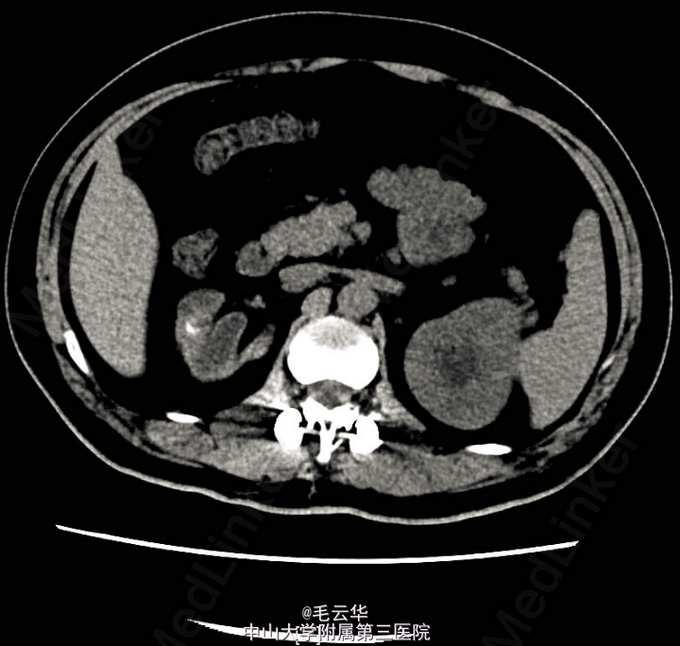

入院诊断:附睾输精管结核,肾结核,肺结核 入院后完善相关检查,尿常规:WBC 232个/ul,RBC 14个/ul。尿抗酸杆菌阴性。CRP阴性,PPD试验阴性。膀胱镜检精阜及后尿道充血明显,余未见异常。胸片未见异常。双肾CTU示右肾、右输尿管结石,右肾萎缩并功能功能重度减退减退,未除外肾结核。带抗结核药(异烟肼、利福平、吡嗪酰胺三联)出院。口服抗结核药治疗2周后返院行腹腔镜下右肾右输尿管切除术。术后继续抗结核治疗。